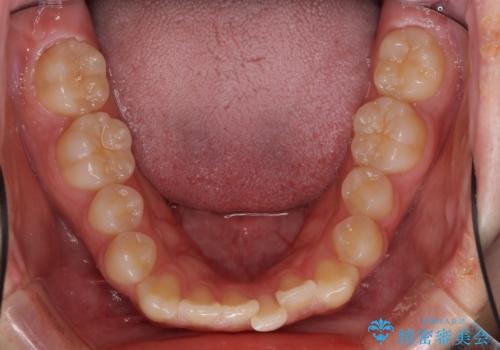

前歯のクロスバイト メタル装置での矯正治療

- 前歯のクロスバイトを気にして来院された患者様です。

前歯の叢生を解消するスペースを獲得するために上顎左右の親知らずを抜歯し、メタルブラケットにて矯正治療を行うこととしました。